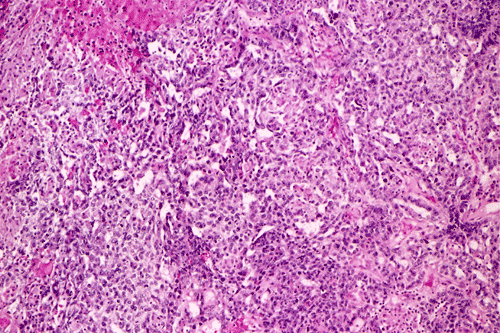

A survey at low-magnification shows a necrotic neoplasm (Panel F). The tumor cells arrange in different patterns. The tumor cells are densely packed in some areas but loosely packed in other areas.  At medium-magnification, several different patterns of architecture are disclosed. The most commonly encountered pattern in this case is a reticular-microcystic arrangement of cells (Panel G). In a significant amount of other areas, there are hypocellular to myxoid non-neoplastic stroma lined by a single layer of neoplastic cells (Panel H, I). The tumor cells have moderate to large nuclei with substantial pleomorphism. The chromatin is clumpy and hyperchromatic (Panel J). In some areas the tumor cells has an hepatoid appearance featured by a smaller nuclei with substantial amount of amphophilic cytoplasm (Panel K). Schiller-Duval bodies are occasionally noted (Panel L). A variable number of eosinophilic globules are also present and they are strongly positive for periodic acid-schiff (PAS) reaction (Panel M). Results of immunohistochemistry are as follows:

Yolk sac tumor arising in the thymus often have extensive invasion into the adjacent tissue. In this cases, the tumor is still confined. The histology is quite typical for a yolk-sac (endodermal sinus) tumor. The reticular-microcystic pattern being illustrated here is the most common pattern being encountered.  Only a small number of Schiller-Duval bodies are present. The large cells with hepatoid look correspond to the hepatoid pattern in yolk sac tumor. The solidly arranged sheets of tumor raise the possibility of an embryonal carcinoma. However, the nuclear pleomorphism, although significant, is still short of that from embryonal carcinoma. The extracellular, PAS(+), eosinophilic hyaline globules are also typical for yolk sac tumor. These globules are often immunoreactive for a-fetal protein and a-1-antitrypsin. In our case, they are only positive for a-1-antitrypsin. The lack of CD30 immunoreactivity, again, does not support a diagnosis of embryonal carcinoma.

Mediastinal non-teratomatous germ cell tumor almost always presents as an anterior mediastinal mass 3. Macroscopically, mediastinal germ cell tumor is a large and soft mass with the size of ranging from 6 to 20 cm in greatest dimension. The cut surface is homogeneous, freshy, and decorated by areas of hemorrhage and necrosis. They are unencapsulated and have inconspicuous boundary. Invasion of the surrounding mediastinal structures is a frequent intraoperative finding. In uncommon cases, mediastinal seminoma may be accompanied by extensive fibrosis. Histologically, mediastinal germ cell tumors have features similar, if not identical, to their gonadal counterparts. Here, we will restrict our discussion to yolk sac tumors.

Yolk sac tumors exhibit a wide range of histologic patterns that differ considerably from each other. In most cases, a mixed histologic pattern is present and, not infrequently, one or two patterns may predominate. The most common pattern is the microcystic-reticular pattern. The other histologic patterns included endodermal sinus, solid, alveolar-glandular, polyvesicular vitelline, myxomatous, macrocystic, papillary, intestinal, hepatoid, and spindle cell. Although there is a rich variation in architecture, the variations in cytologic features are less impressive. The tumor cells are medium to large and have clear to pale, granular cytoplasm. Hobnail cells are not uncommon and often seen with the papillary pattern. The nuclei are large, vesicular, and contain prominent nucleoli. Yolk sac tumors are mitotically active. Necrosis and hemorrhage are common.